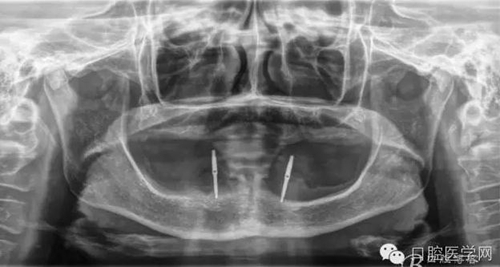

種植體植入后

種植覆蓋全口義齒3個月后上球型基臺